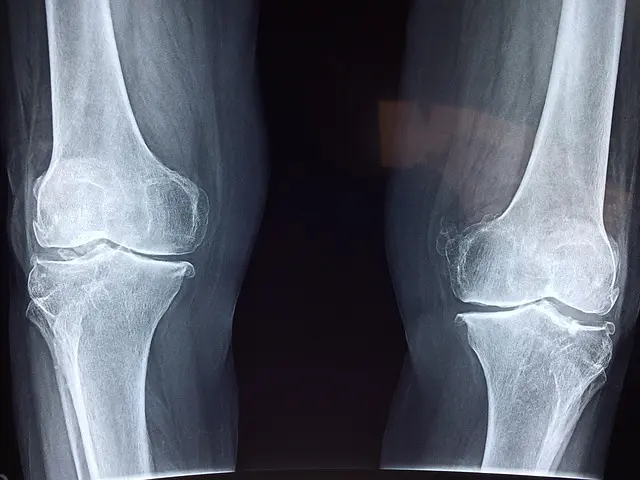

膝の関節には軟骨というクッションの役目をする組織があり、ここにかかる負担が長年積み重なることで少しずつすり減っていきます。軟骨の厚みが減ってくると、関節の中で骨同士の距離が近くなり、動かすたびに負担がかかりやすくなります。